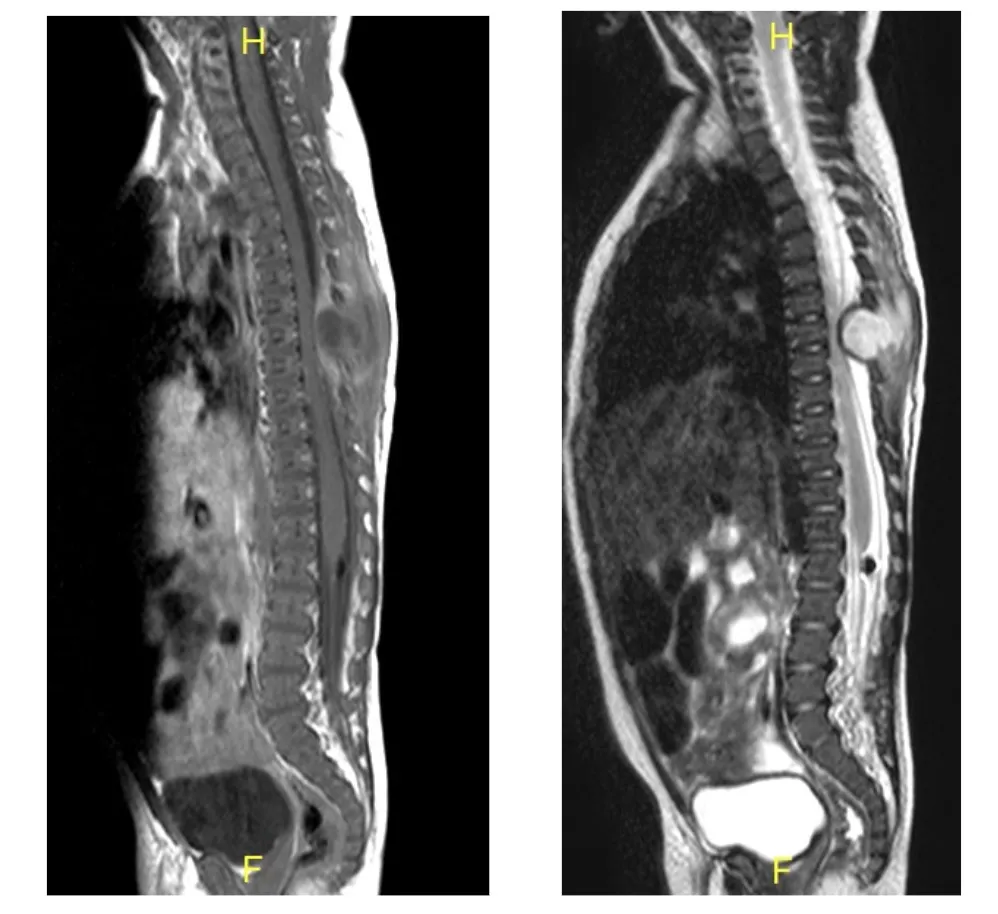

Tuberculosis vertebral

La infección por Mycobacterium tuberculosis, históricamente conocida como enfermedad de Pott, representa una forma particular de espondilodiscitis. Aunque su incidencia ha disminuido significativamente en países desarrollados, continúa siendo relevante en determinadas poblaciones. La tuberculosis vertebral se caracteriza por ser una enfermedad de evolución insidiosa que puede progresar de forma silente durante meses o años, manifestándose únicamente cuando se produce un colapso vertebral que genera una lesión neurológica grave.

Durante la evolución de la espondilodiscitis, el germen destruye progresivamente el disco intervertebral e invade los cuerpos vertebrales. Este proceso destructivo puede provocar consecuencias graves para la estabilidad de la columna y la integridad neurológica.

- Colapso vertebral: la destrucción del disco y de los cuerpos vertebrales puede conducir a un colapso de las vértebras afectadas. Este fenómeno genera una cifosis, es decir, la columna se vence hacia adelante en la zona afectada, alterando significativamente la biomecánica vertebral.

- Inestabilidad vertebral: la pérdida de la integridad estructural de la columna genera una inestabilidad segmentaria que puede comprometer la protección de la médula espinal y las raíces nerviosas.

- Riesgo neurológico: el colapso vertebral, junto con la formación de abscesos epidurales y la inflamación local, pueden comprimir la médula espinal o las raíces nerviosas, generando lesiones neurológicas potencialmente graves e irreversibles si no se tratan a tiempo.